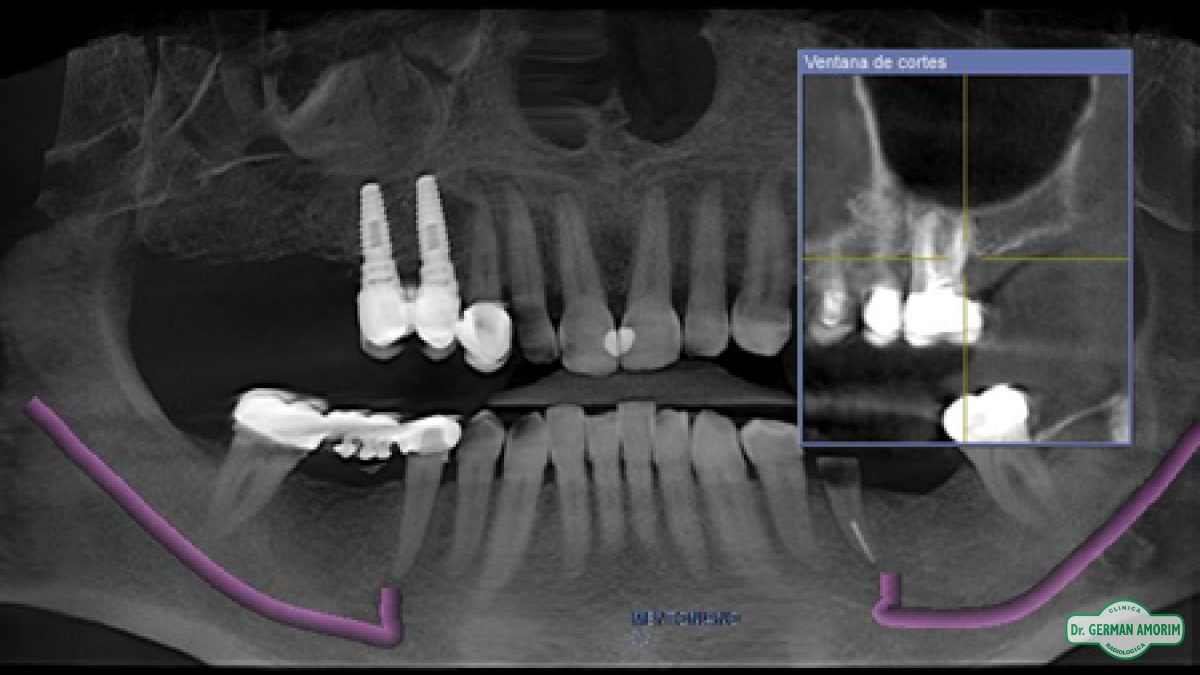

Actualmente y con todos los conocimientos científicos que existen sobre las técnicas implantológicas se recomienda tener siempre una imagen 3D, también en los casos que sea un solo implante. Porque se debe conocer con precisión el espesor de la tabla vestibular para determinar el pronóstico a largo plazo del implante y la única manera de hacerlo es con una tomografía.

En Clínica Amorim contamos con un Tomógrafo de Haz Cónico Orthophos XG de Sirona que mediante la emisión de un haz cónico de rayos genera una serie de imágenes digitales, que son transferidas al computador a partir de las cuales se realiza una reconstrucción en 3D.

El odontólogo utilizando el software específico Galileos puede observar esta imagen en los tres ejes de un espacio tridimensional y trabajar sobre ella para, entre otras cosas, planificar la colocación de los implantes dentales, lesiones ocultas por superposición en las RX convencionales, etc.

Se utiliza para diagnóstico:

• Evaluar si hay hueso suficiente

• Mediciones para ancho y largo del implante

• Determinación de las técnicas de regeneración ósea si es necesario

• Medición de los resultados de las regeneraciones previas a la instalación de implantes y medición de los volúmenes perdidos

• Evaluación de las patologías que pudieran existir

• Determinación de la densidad ósea ya que el sistema permite hacer una densitometría localizada

• Planificación y simulación cirugía de implantes